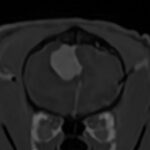

• 【MRI、胸腰部矢状断像、T2強調画像】

画像で見る病気(飼い主様向け)

#19 変性性腰仙椎狭窄症(馬尾症候群)(飼い主様用)

<症例情報> ゴールデンレトリーバー10歳 去勢済みの男の子 主訴:最近腰のあたりを触られ…